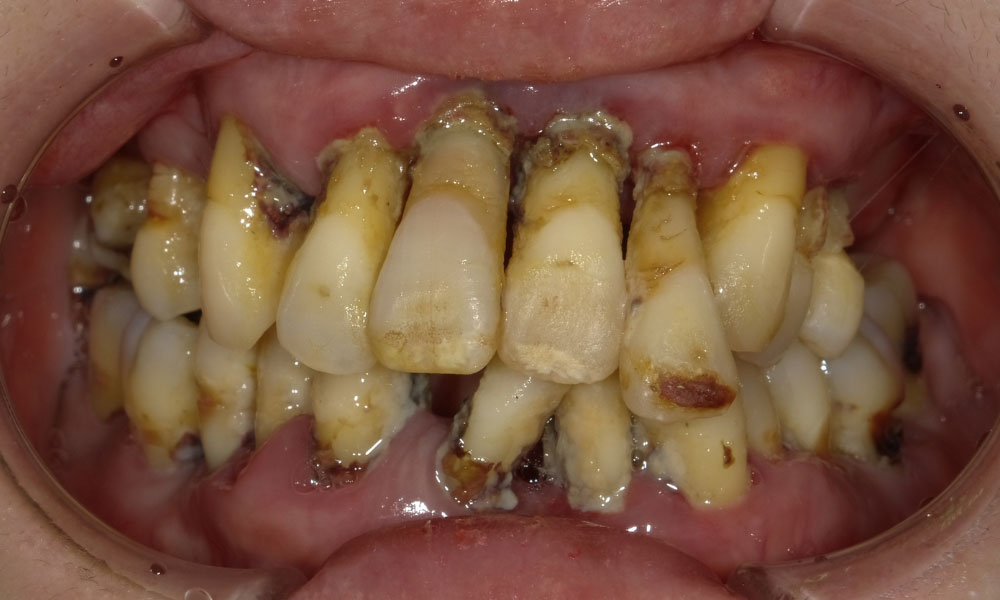

手術前口腔内

症例の詳細

患者情報

50代女性

日帰り全身麻酔により、上下顎同時に手術。